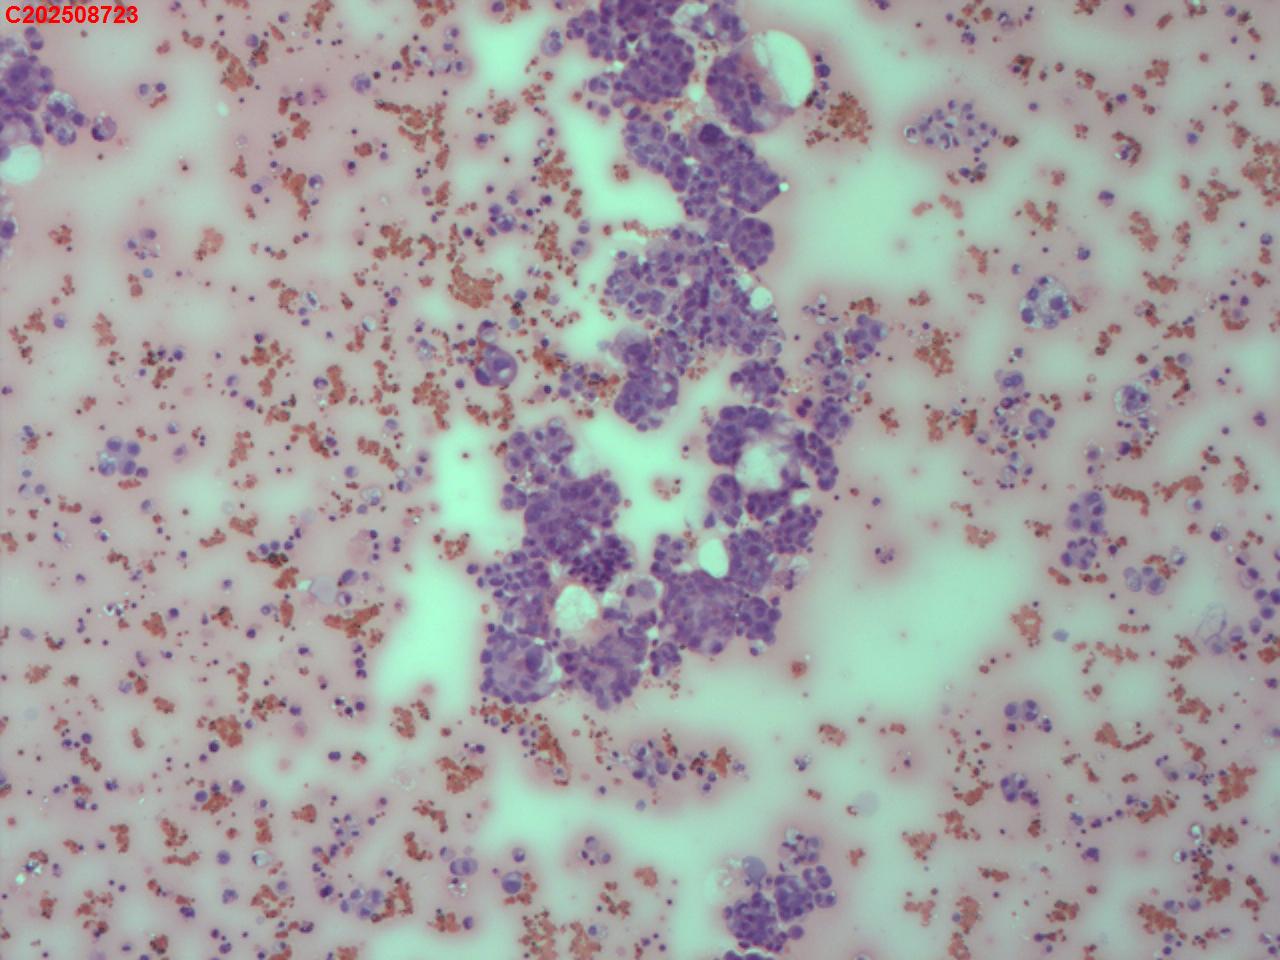

胸水

性别

男

年龄

62岁

胸部CT:提示双肺纹理增多、紊乱,支气管管壁增厚,右肺体积缩小,右侧大量胸腔积液,心包积液,纵膈内淋巴结增多伴部分肿大。

标本类型

制片方法

传统涂片

染色方法

HE染色

腺癌……后续可结合CB及临床资料明确原发灶

倾向腺癌,建议做细胞蜡块行免疫标记协助诊断。